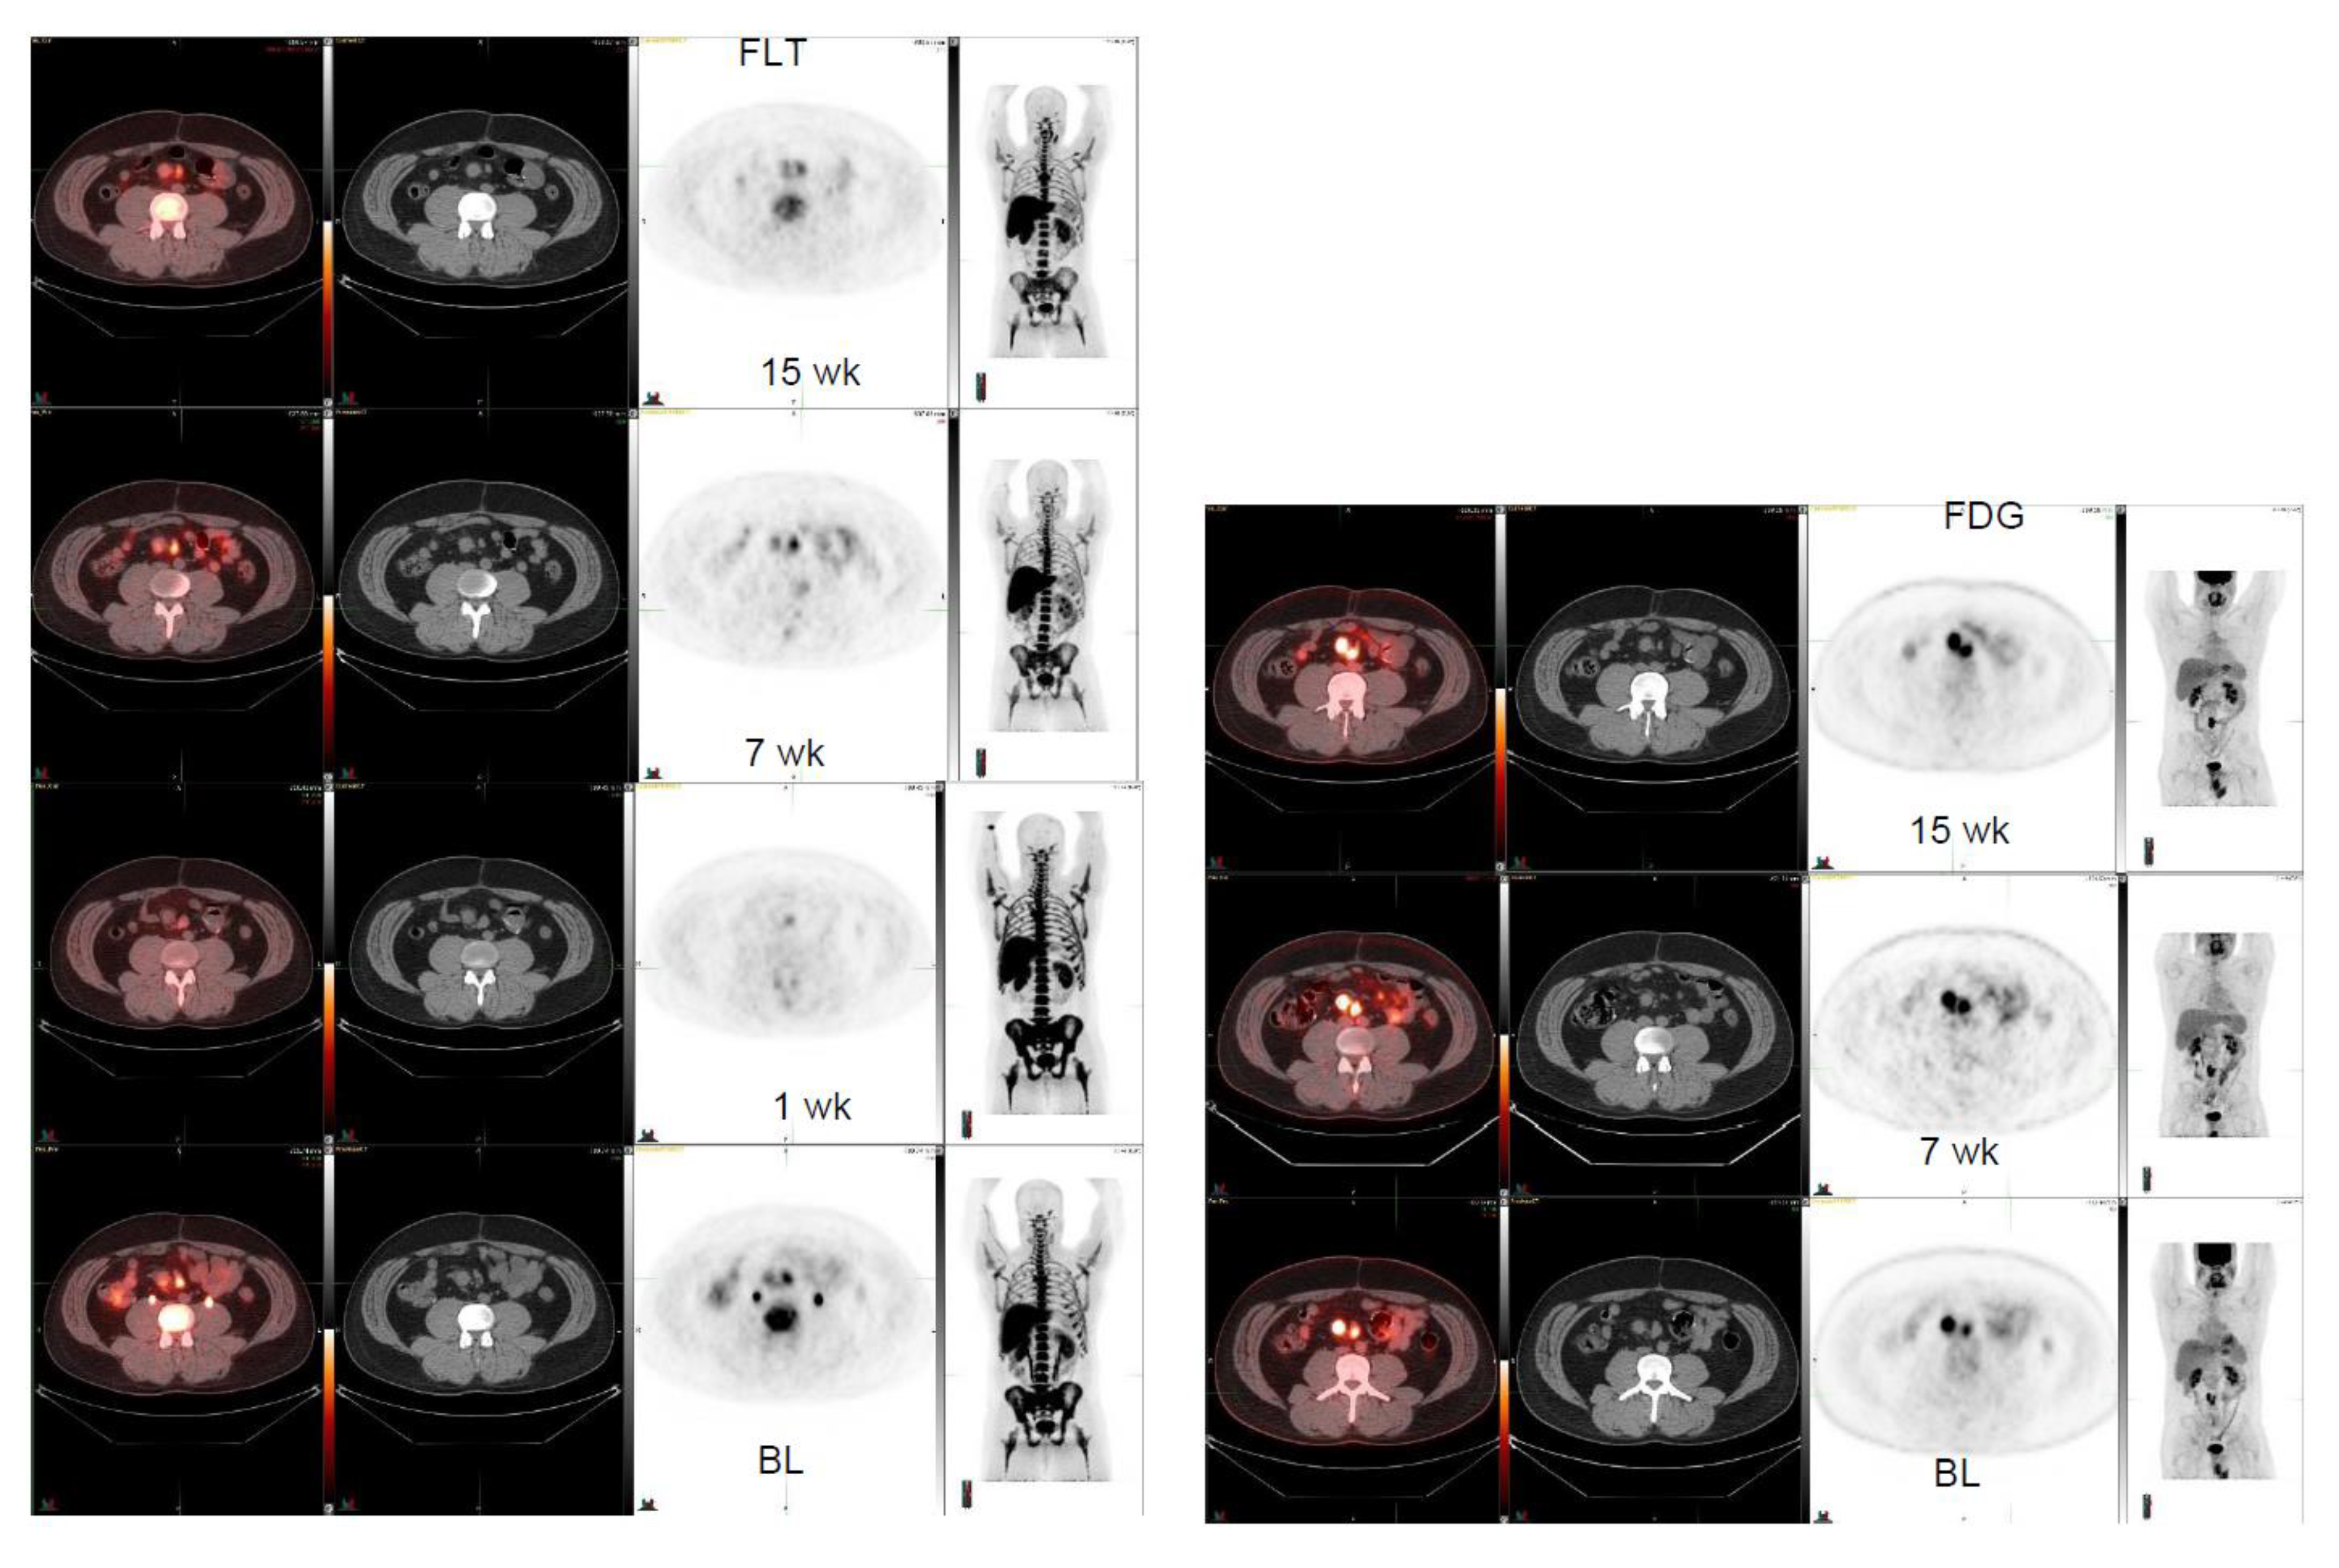

Four patient cases are shown (Figure 1, Figure 2, Figure 3 and Figure 4). A patient with GNET-tumor was studied at baseline and then subsequently at 1, 7, and 15 weeks with 18F-FLT. In addition, the patient also had 18F-FDG-PET imaging study at baseline and at 7 and 15 weeks (Figure 1). This patient had two mesenteric lymph node metastases (annotated R (right) and L(left)); with 18F-FLT, the outcome at seven weeks was -25% (R) and +7% (L), whereas 18F-FDG did not show any response (+19% (R) and +21% (L)). Later, at 15 weeks, the response was clear for 18F-FLT, with a change of −38% (R) and −38% (L), whereas 18F-FDG did not show any clear response (−18% (R) and −2% (L)). A patient with liposarcoma is shown in Figure 2 demonstrating anterior peritoneal mass with three connecting compartments. The patient was studied at baseline and at 1, 8, and 15 weeks with 18F-FLT. FLT-uptakes decreased in the most active site as follows: SUVmax 5.8→4.2 (−28%) →3.5 (−40%). The biggest tumor actually increased in size on CT as follows: 4.1 cm × 3.2 cm →5.5 cm × 4.1 cm→5.6cm × 5.2 cm (Figure 2).

Figure 1.

Gastro neuroectodermal tumor (GNET). FLT-study at baseline, at 1, at 7, and at 15 weeks (left panel, 4 rows). In the right mesenteric lymph node, FLT varies: SUVmax 5.2 ->3.2 -> 3.9->2.8 whereas corresponding sizes change on CT as follows: 2.2 cm × 1.9 cm ->2.0 cm × 1.8 cm->2.0 cm × 2.0 cm ->1.9 cm × 1.7 cm. In the left mesenteric lnn, FLT varies: SUVmax 5.5 ->3.4 -> 5.9->4.0 whereas corresponding sizes change on CT as follows: 2.3 cm × 1.6 cm ->1.9 cm × 1.5 cm->2.1 cm × 1.4cm ->2.0 cm × 1.2 cm. FDG-study at baseline, at 7, and at 15 weeks (right panel, 3 rows). In the right mesenteric lnn, FDG varies: SUVmax 12.9 ->nm -> 15.4->10.6 and in the left mesenteric lnn: SUVmax 8.2 ->nm -> 9.9->8.0.

Here, we have shown that multiple sarcoma subtypes can be imaged using FLT (Figure 1, Figure 2, Figure 3 and Figure 4. Figure 1 demonstrates that FDG uptake increases early, whereas FLT remains stable or decreases. The FDG uptake may also demonstrate pseudoprogression, which is typical for immunotherapies. Similarly, in Figure 3, the FLT uptake decreases and FDG uptake increases. We also see that the decrease in cell proliferation can be imaged using FLT in spite of the SUV level (Figure 1, Figure 2, Figure 3 and Figure 4).